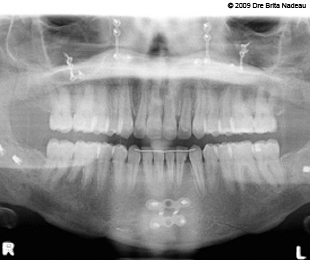

- Introduction

- Guide de l'opéré

- Mon histoire

- Photos & radiographies